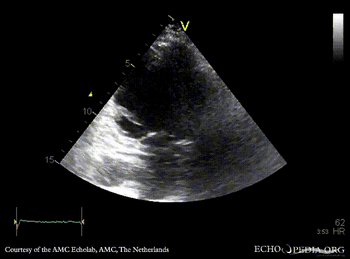

A4CH: dilated left ventricle, poor function, akinesia of inferoseptal wall A2CH: dilated left ventricle, poor function, akinesia of inferior wall

A3CH: dilated left ventricle, poor function, akinesia of posterior wall